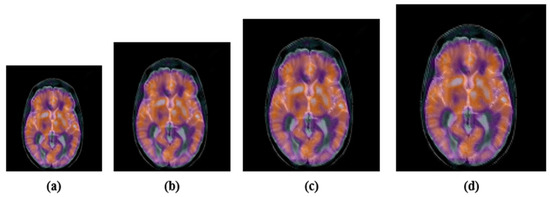

4.2.2. Geometric Attacks